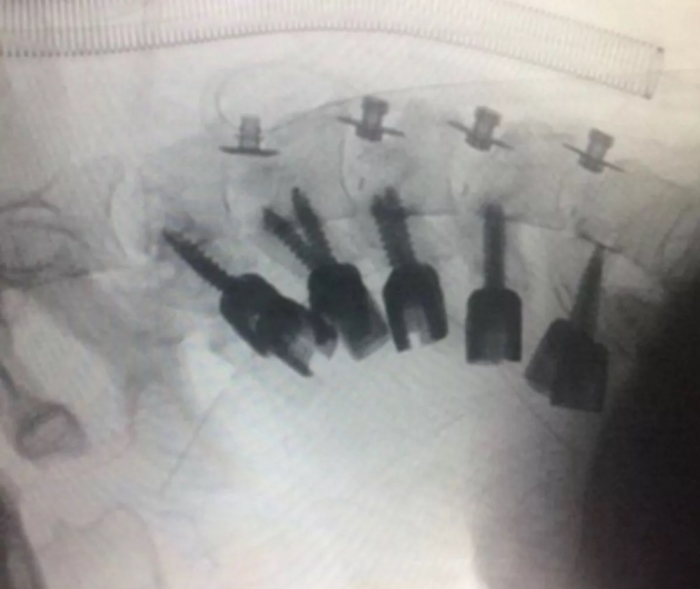

ภาพจาก Al-Zahra University Hospital

ภายหลังจากการตรวจเช็กร่างกายโดยละเอียด พบว่า ผู้ป่วยไม่มีอาการผิดปกติทางระบบประสาท แต่ผลการทำซีทีสแกนแสดงให้เห็นว่า กระดูกสันหลังของผู้ป่วยรายนี้ผิดรูปอย่างรุนแรง จำเป็นต้องทำการผ่าตัดเพื่อรักษาอาการ โดยแพทย์ต้องเอากระดูกที่ผิดรูปออกและใช้เทคนิคการผ่าตัดพิเศษเพื่อพยุงศีรษะขึ้น จนในที่สุดการผ่าตัดก็ประสบความสำเร็จ

โดยหลังจากผ่าตัดได้ 1 วัน ผู้ป่วยสามารถเดินได้โดยใช้ปลอกคอแบบแข็ง ซึ่งเขาต้องสวมปลอกคอนี้ต่อไปนาน 3 เดือน รวมทั้งต้องเข้ารับการบำบัดอาการติดยาด้วย